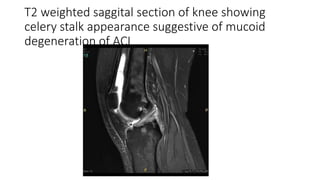

• Mucoid degeneration of ACL-Age related degeneration in which

secondary signs of an ACL injury like bone bruise, meniscus tears and

anterior translation of tibia is absent.

T2 weighted saggital section of knee showing

celery stalk appearance suggestive of mucoid

degeneration of ACL

T2 weighted saggitalsection of knee showing celery stalk appearance suggestive of mucoid degeneration of ACL